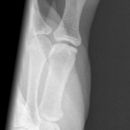

Endgelenksluxation Daumen